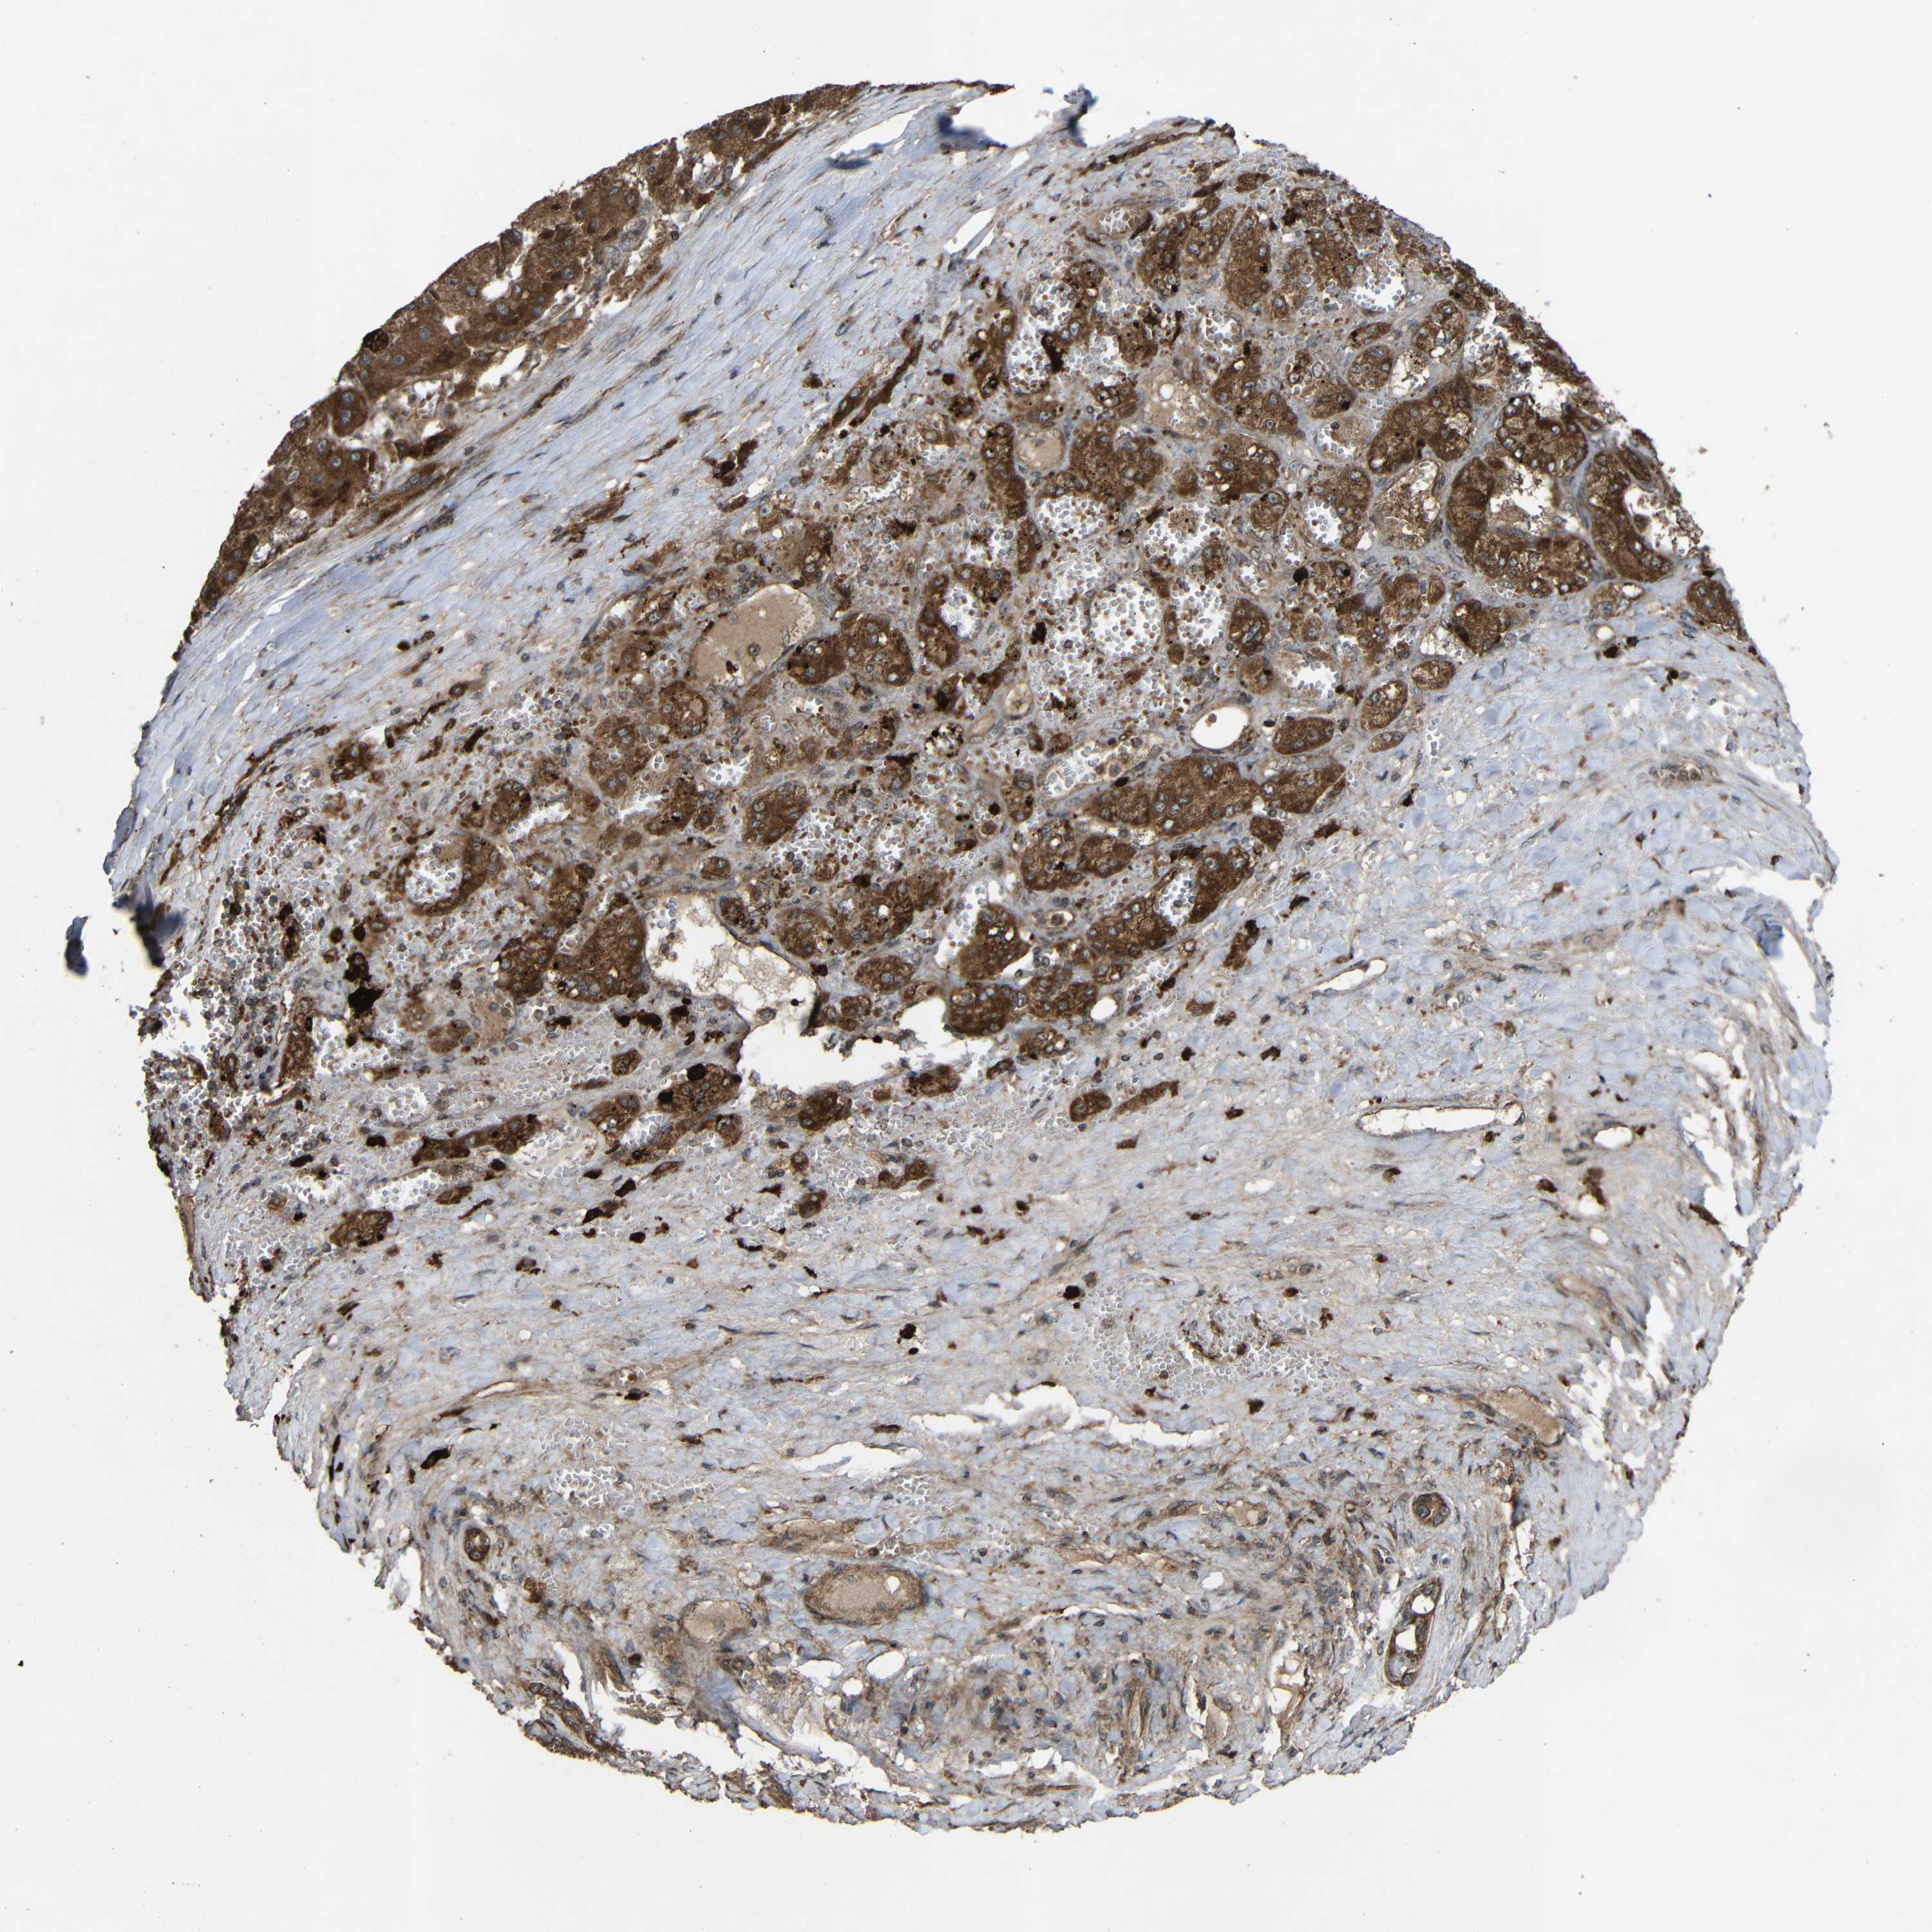

LIVER CANCER - Protein expressioni

A mouse-over function shows sample information and annotation data. Click on an image to view it in a full screen mode. Samples can be filtered based on level of antibody staining by selecting one or several of the following categories: high, medium, low and not detected. The assay and annotation is described here.

Note that samples used for immunohistochemistry by the Human Protein Atlas do not correspond to samples in the TCGA dataset.

Antibody stainingi

Antibody staining in the annotated cell types in the current human tissue is reported as not detected, low, medium, or high, based on conventional immunohistochemistry profiling in selected tissues. This score is based on the combination of the staining intensity and fraction of stained cells.

Each image is clickable and will lead to virtual microscopy that enables deeper exploration of all samples and also displays staining intensity scores, fraction scores and subcellular localization as well as patient and tissue information for each sample.

Antibody HPA011294

Antibody HPA012819

Staining

High

Medium

Low

Not detected

Intensity

Strong

Moderate

Weak

Negative

Quantity

>75%

75%-25%

<25%

None

Location

Nuclear

Cytoplasmic/membranous

Cytoplasmic/membranous,nuclear

Cholangiocarcinoma

Carcinoma, Hepatocellular, NOS